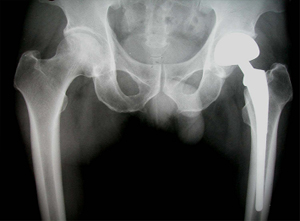

• 수술 전 고관절 X-선 수술 전 고관절 X-선 사진

• 고관절 치환술 후 X-선 고관절 치환술 후 X-선 사진